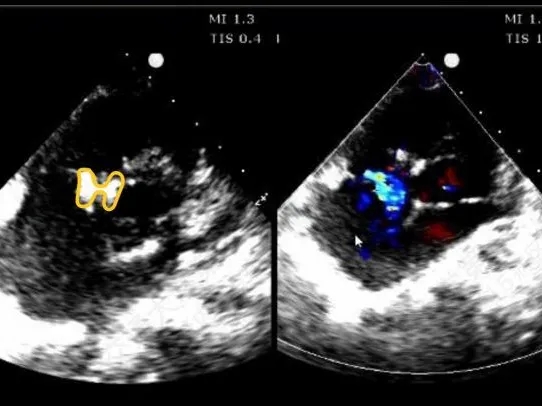

术前超声与DSA复测

VSD(膜周部):室间隔膜部瘤,左室面6.5mm,右室面呈“瘤样”结构,瘤体深度7mm,出口2mm。

形态与术前超声差别:

该病灶呈现为“长隧道、大瘤底、小出口”的细腰形态,且位置紧邻主动脉瓣与三尖瓣,解剖结构较为复杂。此形态特征使得可降解封堵器在植入过程中的定位与释放面临较大挑战。